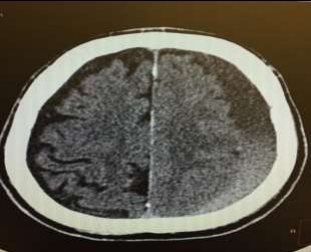

Fig 1,2,3,4,5,6,7,8,9,10,11,12,13,14,15

Thirty eight out of Eighty-two patients were treated conservatively and were studied (25 men; 13 females, mean age, 64.8 years). The average thickness of the hematoma was 18 mm, the mean midline shift was 4.7 mm, and the average attenuation value of bleed on computed tomography scan was 33.5. Thirty-eight were treated successfully with steroid treatment, whereas 44 patients required surgery. The female gender, less midline shift, less density (Hounsfield units) was noted to be associated with successful medical treatment. We propose a grading based on the total score given to the midline shift and density.

Figure 1

Figure 2

Figure 3

Figure 4

Figure 5

Figure 6

Figure 7

Figure 8

Figure 9

Figure 10

Figure 11

Figure 12

Figure 13

Figure 14

Figure 15